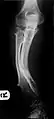

Multiple osteochondromas causing deformity of the forearm (shortening of the Radius with secondary bowing of the Ulna).